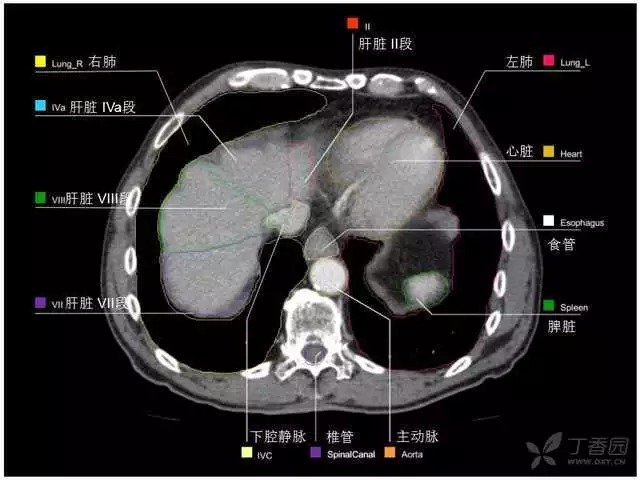

腹部肝脏高清CT断层的图谱

全腹部高清CT图谱,淋巴结彩色图谱,血管解剖图谱大汇总!

肝段,肝内管道的分布规律

美国放射学会ACR官网,对肝脏的区域和节段解剖学概述